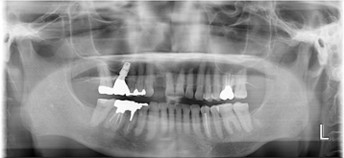

70代 女性

治療前

治療後

治療後- リスク・副作用

- 術後疼痛、歯肉腫脹

- 治療の費用

- 合計¥587,000(税込)

【内訳】

インプラント(1本)¥440,000

その他費用¥147,000

(薬・注射・レントゲン・CT・データ分析・サージカルステント・血液検査) - 年齢/性別

- 70代/女性

- 患者の具体的な症状

- 下顎の奥歯が義歯で噛みづらいため、インプラント治療を希望

- 検査方法

- コーンビームCT、レントゲン撮影

- 診断結果

- 左下6欠損

- 治療詳細

- 左下6インプラント埋入1本、骨造成なし、局所麻酔

- 通院回数

- 8回

- 治療期間

- 6か月